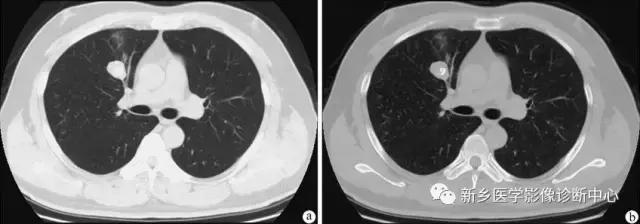

支气管囊肿(单发)

年轻人30Y多发,无明显症状或有咳嗽,发热,胸痛,脓性痰等。以下肺野内带常见。类圆形水样密度影,无钙化,一般在10HU以下,含粘液时CT值增高,可与支气管相通成为含气囊肿。